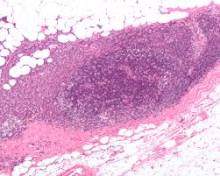

How chronic inflammation can lead to cancer Chronic inflammation caused by disease or exposure to dangerous chemicals has long been linked to cancer, but exactly how this process takes ...